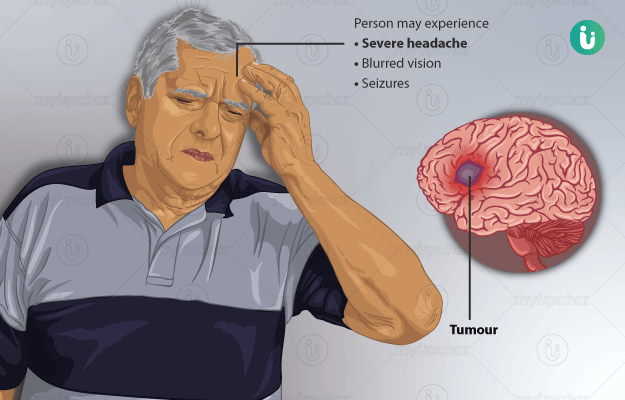

लग त र स र दर द ह सकत ह ब र न ट य मर क स क त ज न लक षण और इल ज brain tumor sign continue headache know brain tumor symptoms and treatment news nation (फाइल का प्रकार jpg)

लग त र स र दर द ह सकत ह ब र न ट य मर क स क त ज न लक षण और इल ज Brain Tumor Sign Continue Headache Know Brain Tumor Symptoms And Treatment News Nation